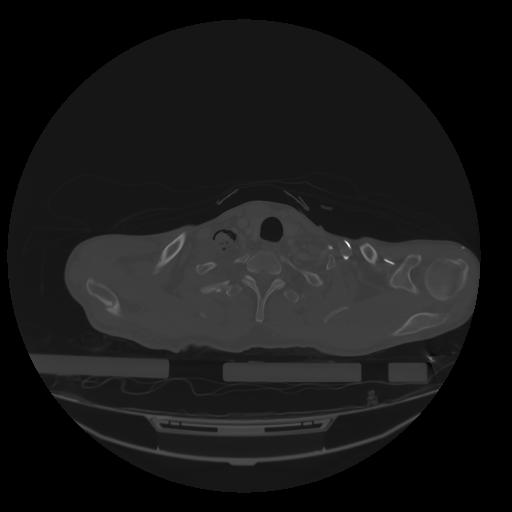

28 CUERPO,CE,Vol,2.0,CUERPO,,